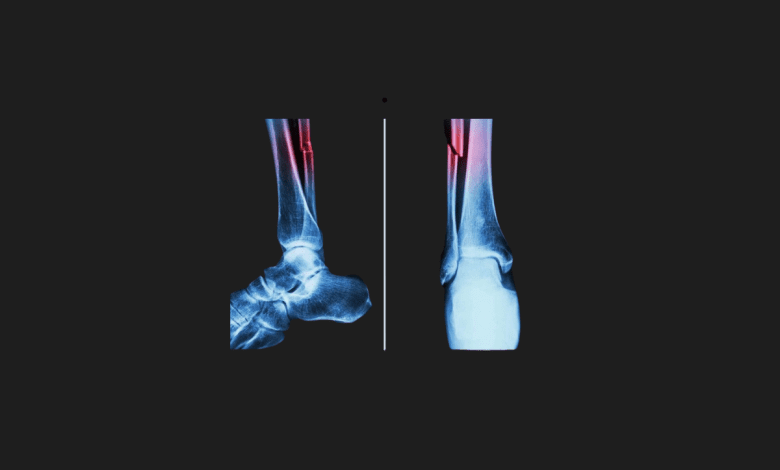

The medical world continues to develop new methods for faster and more effective fracture treatments. Biomedical projects that push the limits of traditional surgical techniques are emerging one after another. You may recall a notable project in this direction from South Korea a few weeks ago, which introduced a special “hot glue gun” aimed at repairing fractures. Now, a project from China has taken this field’s advancement to a whole new dimension. The new adhesive developed by Chinese scientists, named “Bone-02,” can repair bone fractures within three minutes with just a single injection.

Technical tests report that the adhesive’s bonding strength is over 180 kilograms, its shear strength is approximately 0.5 megapascals, and its compressive strength is around 10 megapascals. These values indicate that the adhesive provides a permanent repair capable of bearing the forces a bone is subjected to in daily life, not just a short-term fixation.